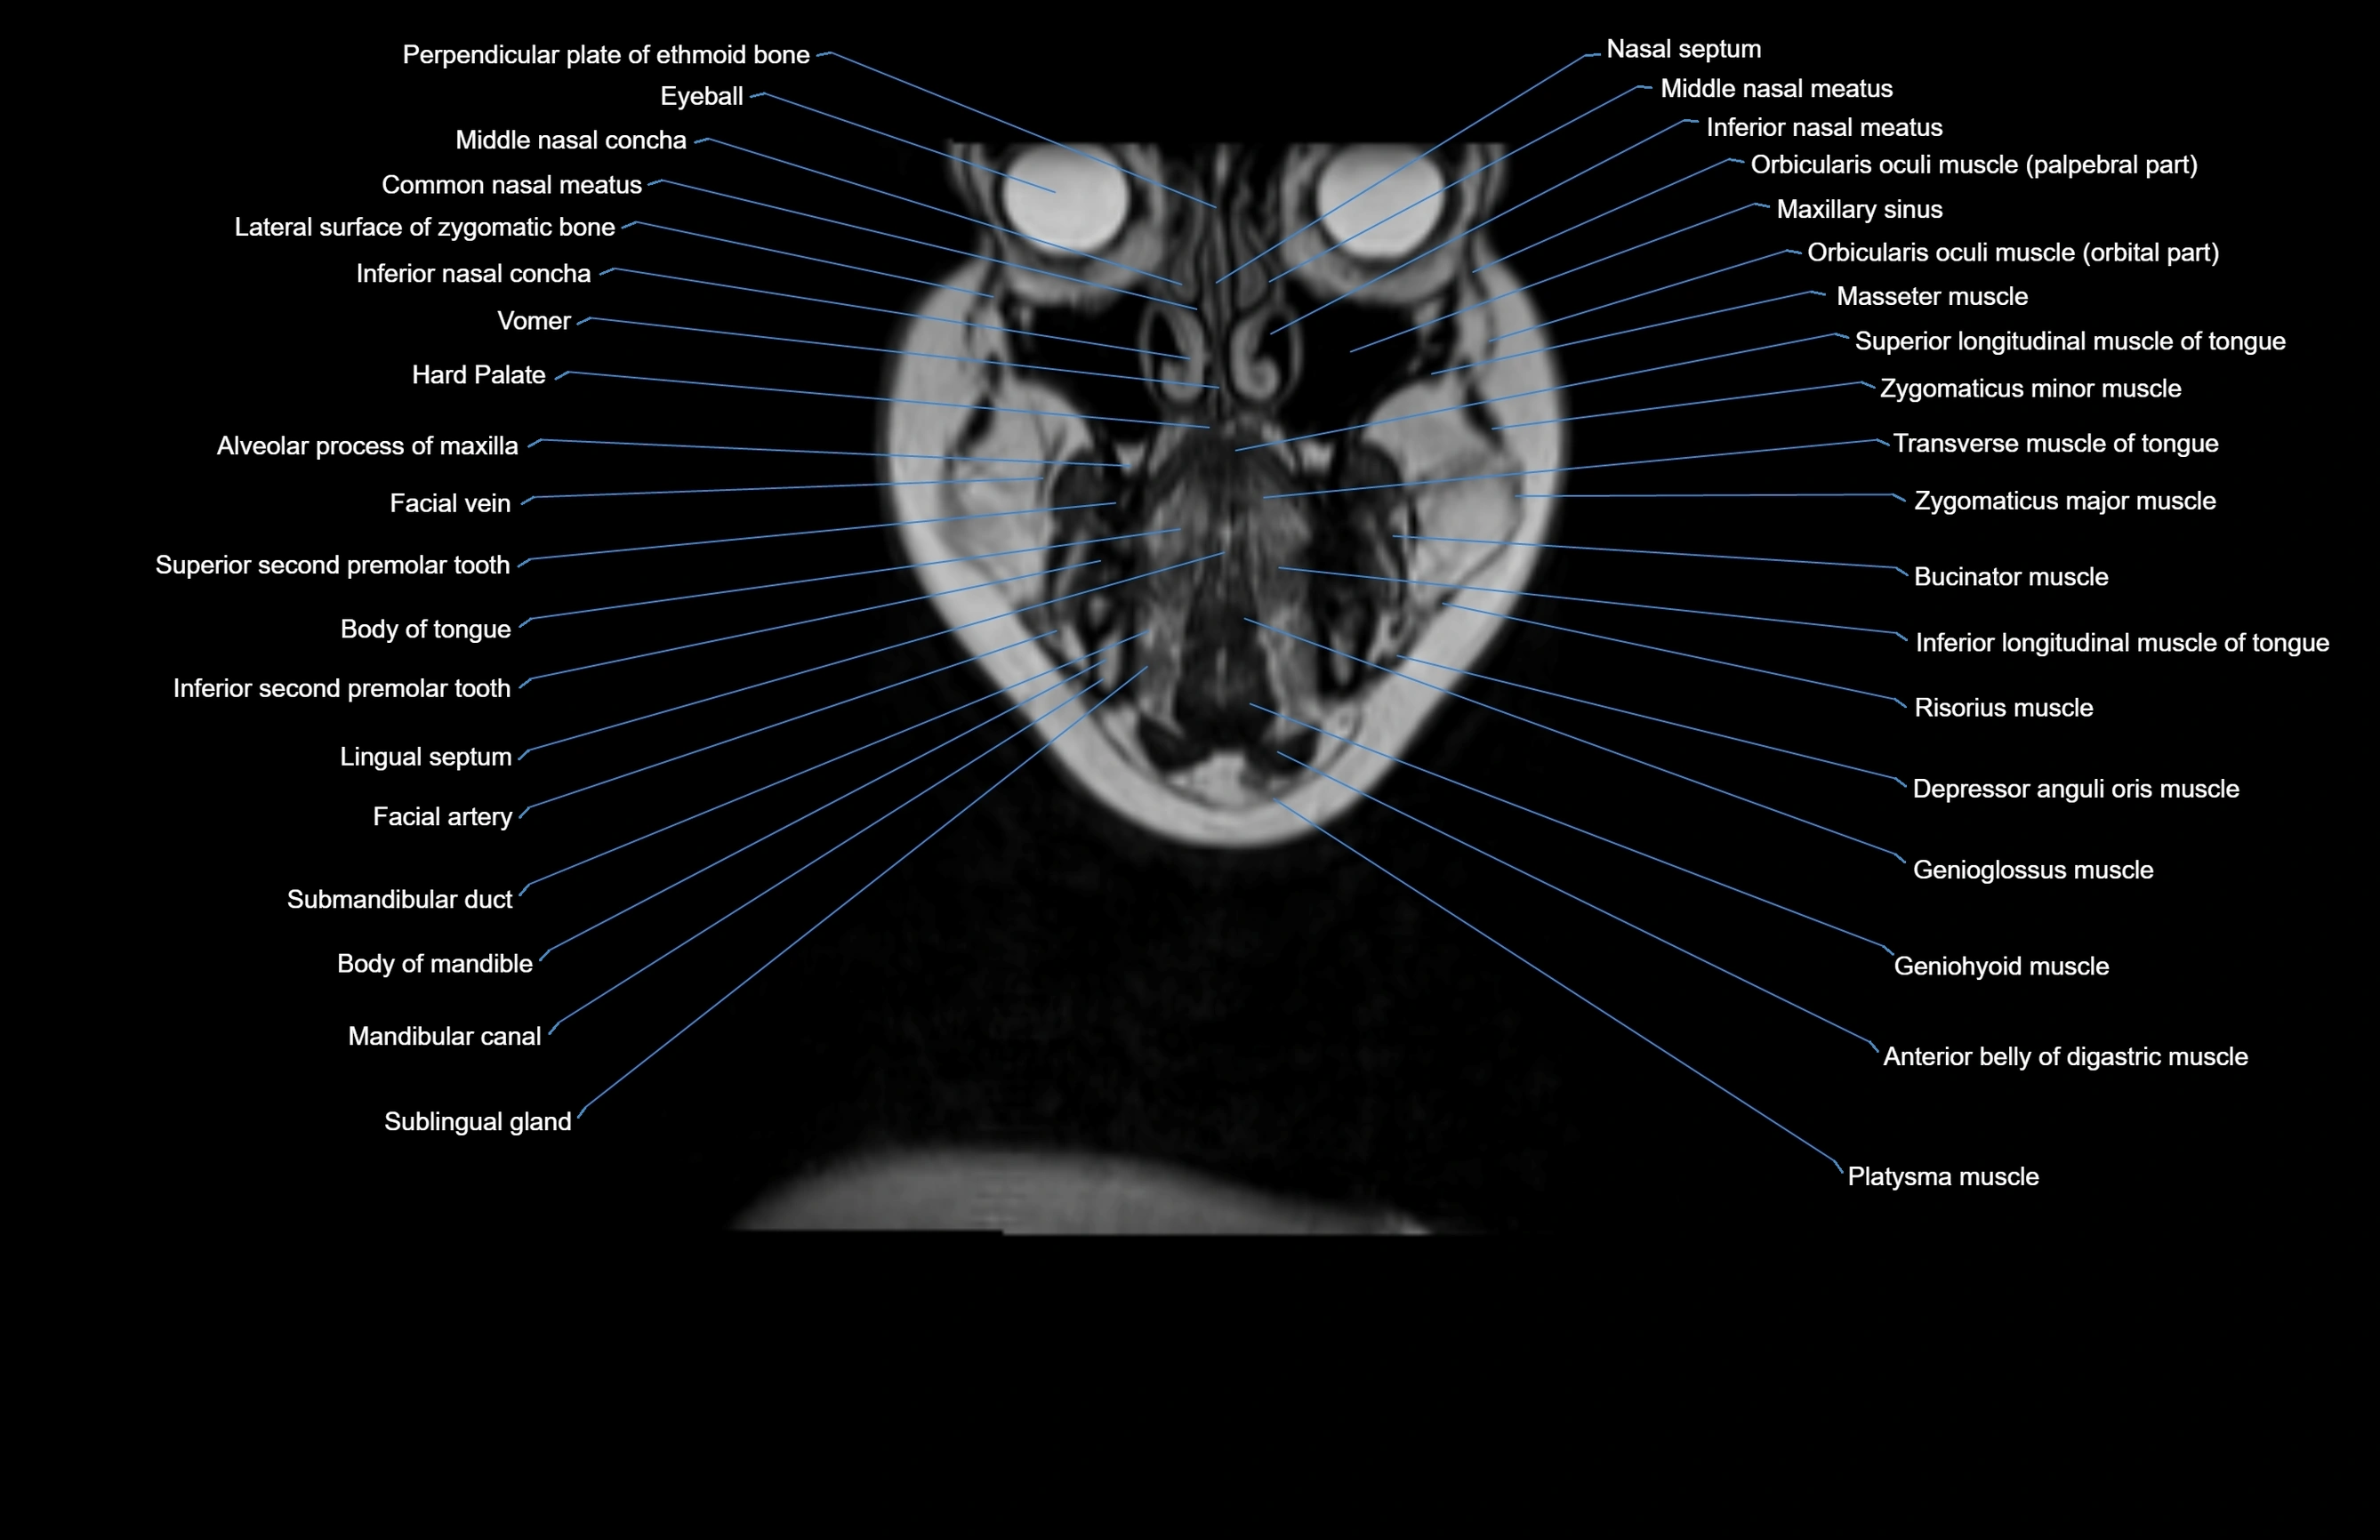

- Alveolar process of maxilla

- Body of mandible

- Body of tongue

- Buccinator muscle

- Common nasal meatus

- Depressor anguli oris muscle

- Eyeball

- Genioglossus muscle

- Inferior longitudinal lingual muscle

- Inferior longitudinal muscle of tongue

- Inferior nasal concha

- Inferior nasal meatus

- Mandibular canal

- Maxillary sinus

- Orbicularis oculi muscle (Orbital part)

- Orbicularis oculi muscle (Preseptal part)

- Platysma muscle

- Risorius muscle

- Sublingual gland

- Submandibular duct